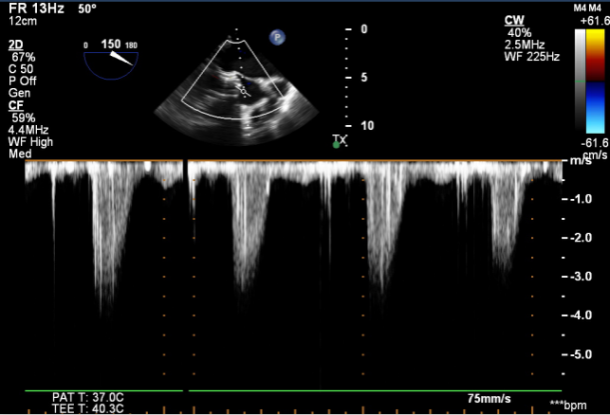

图2.CDFI示主动脉瓣血流信号呈“五彩”样,CW示过瓣流速明显增快

图6.TEE提示未见瓣周漏,CW示过瓣流速较术前明显下降